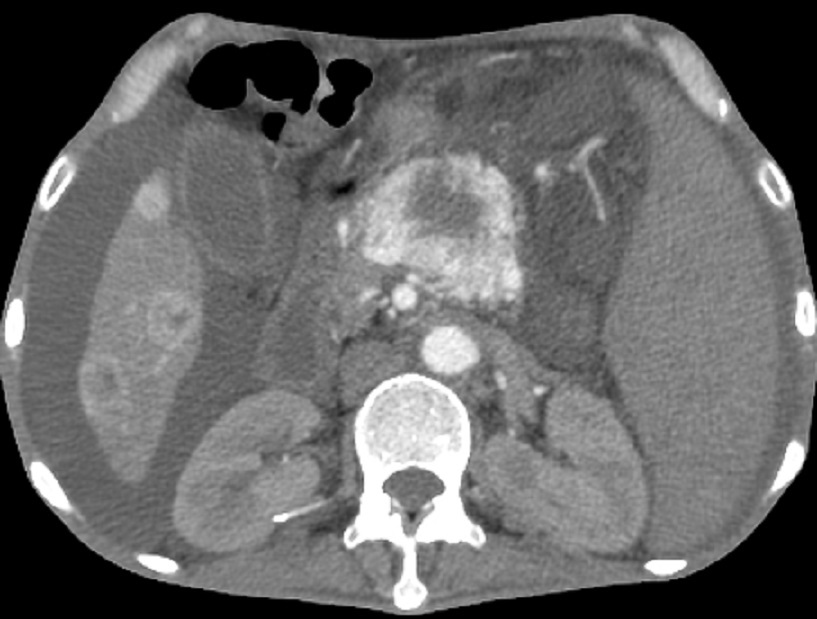

-

Les tumeurs endocrines non fonctionelles souvent

decouverte tardive a volumineuse , taille moyen 10cm ,

souvent necrose hemorragique central , en association de

bourgeon neoplesique vieneuse de veine splenique ou

veine mesenterique superieure et metastase hepatique (

90% des cas )

Les tumeurs endocrines

non fonctionelle sont rare et souvent en decouverte

tardive , tres volumneuse a taille depasse 10cm .

Aspect radiologique TDM de ce tumeur est hypodense

heterogene a tres grand taille situe au queue du

pancreas . Coupe TDM C+ |

Image radiologique

d'un tumeur endocrine non fontionelle du queue

pancreas a grand taille . Ce que entraine une

deformation neoplasique du systeme veine splenique .

Image vde engainement veineuse et abrution

neoplasique de veine splenique ( fleche rouge c) |

90% des tumeurs endocrines

non fontionelles avaient de lesions metastasiques

locaux ou a distance . Image radiologique TDM du

metastase hepatique foie droit d'un tumeur

pancreatique non fontionelle ( fleche rouge ) |

Image radiologique TDM plus C +

d'un tumeur endocrine non fontionelle du pancreas

avec des nodules metastasique du foie . Aspect

hypervascularise hyperdense avec zone necrose

parenchymateuse hypodense central se voyait tres

nette . Coupe radiologique TDM axiale avec contrast

intraveineuse au phase arterielle |